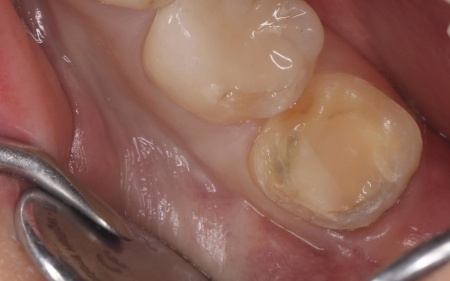

40代女性 欠けたセラミックインレーを除去してオンレータイプの被せ物で修復した症例

拝見したところ、左下の一番奥の歯には歯の一部を覆う白い詰め物であるセラミックインレーが装着されていましたが、日常的に力が加わったことで、右上奥歯と接触する部分のセラミックが欠けていました。

このまま放置すると、欠けた部分から細菌が侵入して虫歯の原因になったり、さらに大きな破折につながったりするリスクがあります。

患者様は審美性と長期間使用できる耐久性を重視されていたため、従来の小さなインレータイプではなく、より広い範囲で歯の噛む面全体を覆うオンレータイプでの修復治療を提案しました。

まず、破折した既存のセラミックインレーを慎重に除去します。

続いてオンレーが適切に装着できるよう、精密に歯の形を整えました。歯を削る際は、健康な歯質をできるだけ残せるよう配慮しています。